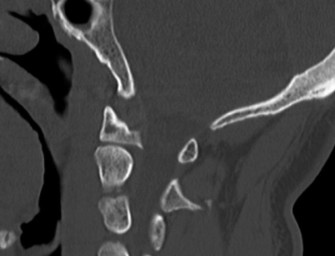

Radiographic and Computed Tomography Evaluation

Initial trauma radiographs demonstrated a loss of anterior and middle column height at L1, with a focal kyphotic deformity. However, plain films are vastly insufficient for definitive surgical planning in thoracolumbar trauma. A high-resolution, fine-cut Computed Tomography (CT) scan of the entire spine was obtained. The CT images confirmed an L1 burst fracture with severe comminution of the vertebral body. Sagittal and axial reconstructions revealed 50% canal compromise secondary to a large retropulsed bone fragment originating from the posterosuperior aspect of the L1 vertebral body. Furthermore, the CT demonstrated 25 degrees of segmental kyphosis measured from the superior endplate of T12 to the inferior endplate of L1.

A critical finding on the axial CT slices was a vertical, split fracture propagating through the L1 lamina. This is a highly significant morphological feature. A lamina fracture in the setting of a burst fracture with retropulsion strongly correlates with a dural tear and potential entrapment of the cauda equina nerve roots. When the vertebral body bursts posteriorly, the pedicles are driven outward, and the lamina fractures as the spinal canal attempts to expand to accommodate the retropulsed bone. If the dura is lacerated, nerve roots can herniate through the dural defect and become incarcerated in the laminar fracture site.